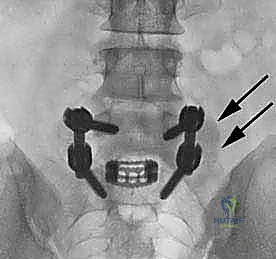

في هذه التقنية، يتم الوصول إلى العمود الفقري من الخلف مباشرة. يقوم الجراح بإزالة جزء من العظم (الصفيحة الفقرية Laminectomy) للوصول إلى القناة الشوكية. يتم سحب الأعصاب برفق إلى الجانبين للوصول إلى القرص التالف وإزالته، ثم يتم إدخال "أقفاص" (Cages) مدعومة بطعوم عظمية من كلا الجانبين.

تقنية TLIF (الاندماج الفقري القطني عبر الثقب)

تُعد TLIF تطوراً لتقنية PLIF. بدلاً من الدخول مباشرة من المنتصف وسحب الأعصاب بشكل كبير، يتم الوصول إلى القرص الغضروفي من جانب واحد عبر "الثقبة" (Foramen) - وهي الفتحة التي يخرج منها العصب.

| عدد الأقفاص (Cages) | يتم وضع قفصين (واحد في كل جانب). | يتم وضع قفص واحد كبير مائل. |

الخطوة 4: زراعة القفص والطعم العظمي (Cage Insertion)

يتم إدخال قفص مصنوع من مادة PEEK أو التيتانيوم، مملوء بطعم عظمي (يؤخذ غالباً من المريض نفسه أو طعم صناعي)، في المساحة الفارغة. هذا القفص يعيد الارتفاع الطبيعي للفقرات ويخفف الضغط عن منافذ الأعصاب.